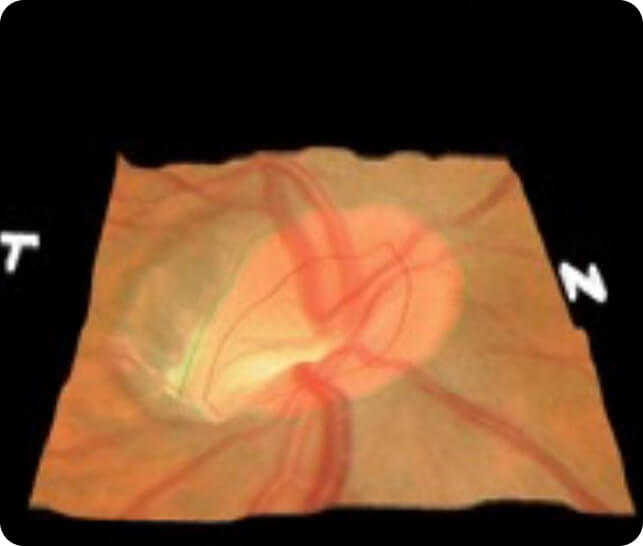

Optic Nerve Imaging

• KOWA stereo imaging system

• At Edgbaston Eye Clinic, we are the only private clinic in Edgbaston offering the advanced Optos (Daytona) ultrawide field imaging system for both retinal imaging and optic disc capture, crucial in the early detection and management of glaucoma

• The Optos (Daytona) provides a 200-degree view of the retina, enabling comprehensive evaluation of the optic nerve head and retinal nerve fibre layer (RNFL), areas commonly affected by glaucoma

• This imaging system allows us to detect optic disc changes, such as cupping, which is a key indicator of glaucoma progression

• The high-resolution images captured by the Optos help us identify and monitor conditions like glaucoma, diabetic retinopathy, and macular degeneration, ensuring accurate diagnosis and treatment

• Optos imaging is non-invasive, fast, and provides immediate results, making it an essential tool for both routine eye exams and detailed glaucoma assessments

• By utilising this cutting-edge technology, Edgbaston Eye Clinic offers unparalleled glaucoma care and optic disc monitoring, ensuring the best outcomes for our patients